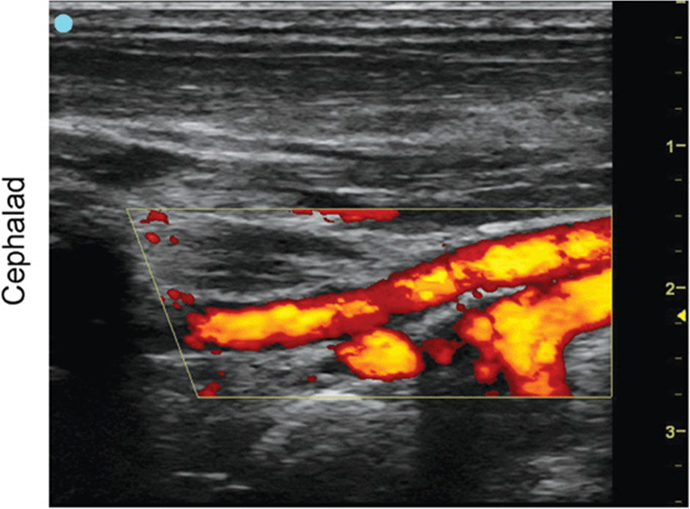

Mandibular Nerve

FIGURE 7.2.1A Ultrasound transducer position to image the mandibular nerve.

FIGURE 7.2.1B Ultrasound image of mandibular nerve.

FIGURE 7.2.1C Labeled ultrasound image of mandibular nerve.

FIGURE 7.2.1D Labeled ultrasound image of mandibular nerve with color Doppler.